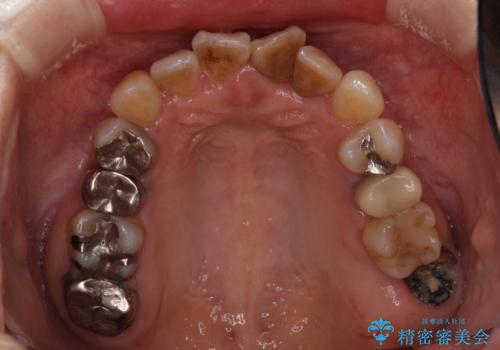

骨格的に下顎が前方位にありますが、歯列矯正で前歯の被蓋関係を改善することができると判断されたため、インビザラインにより矯正治療を行うこととしました。

また、上顎前歯と下顎大臼歯に神経を取り除いた歯があったため、矯正治療後に、セラミッククラウンにて補綴することとしました。